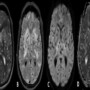

•Imaging shows extensive lesions diffusely distributed in brain parenchyma with variable degree of perilesional edema and enhancement giving the picture of starry sky.